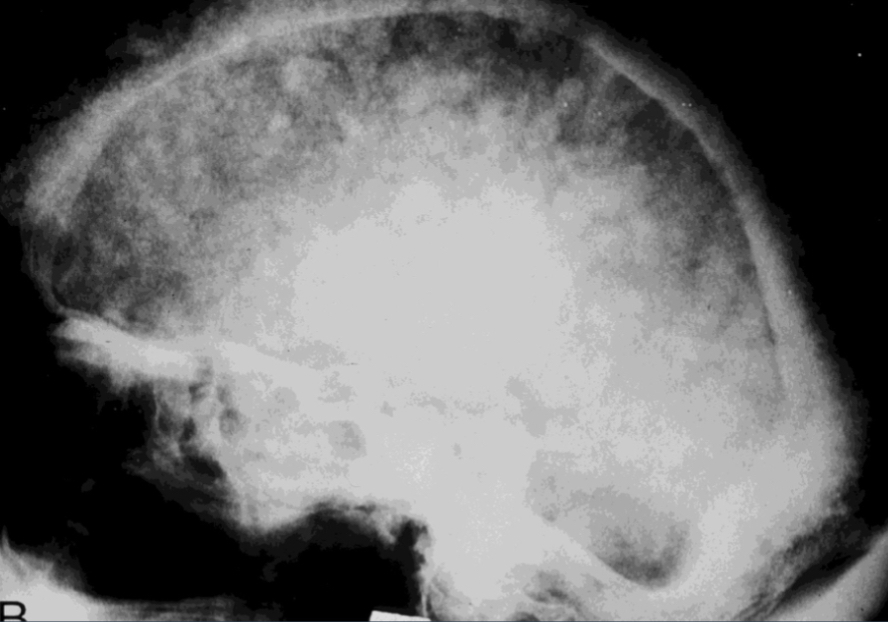

what is this?

how do you describe it?

paget disease

cotton wool appearance basilar impression (tip of the odontoid process projects above the foramen magnum)